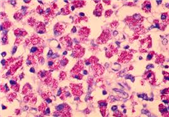

(세균) Mycobacterium spp.

M. avium

출처:http://phil.cdc.gov/phil/details.aspID#965, CDC/Dr. Edwin P. Ewing, Jr.